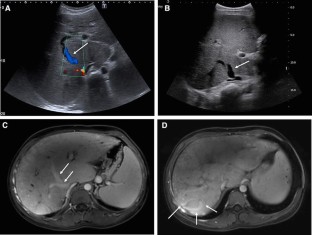

Fig. 1